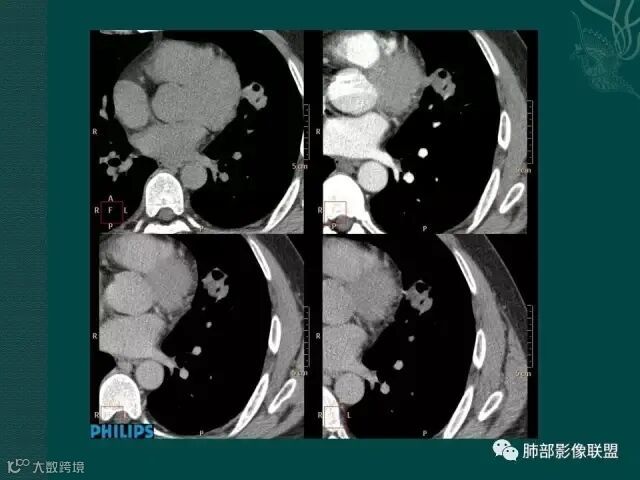

病史似乎是炎性;空洞型病变,靠近纵隔的时候,一定要看对纵隔是否有侵蚀,这是相当重要的。

红箭头所指是右上肺静脉,起始部是完好的,上一层被病变完全包埋,管腔变窄,管壁形态不规则,并侵犯相邻纵隔。

肺癌靠近纵隔时,对纵隔的侵犯,对诊断有重要诊断价值,炎症的话很少会侵犯血管。